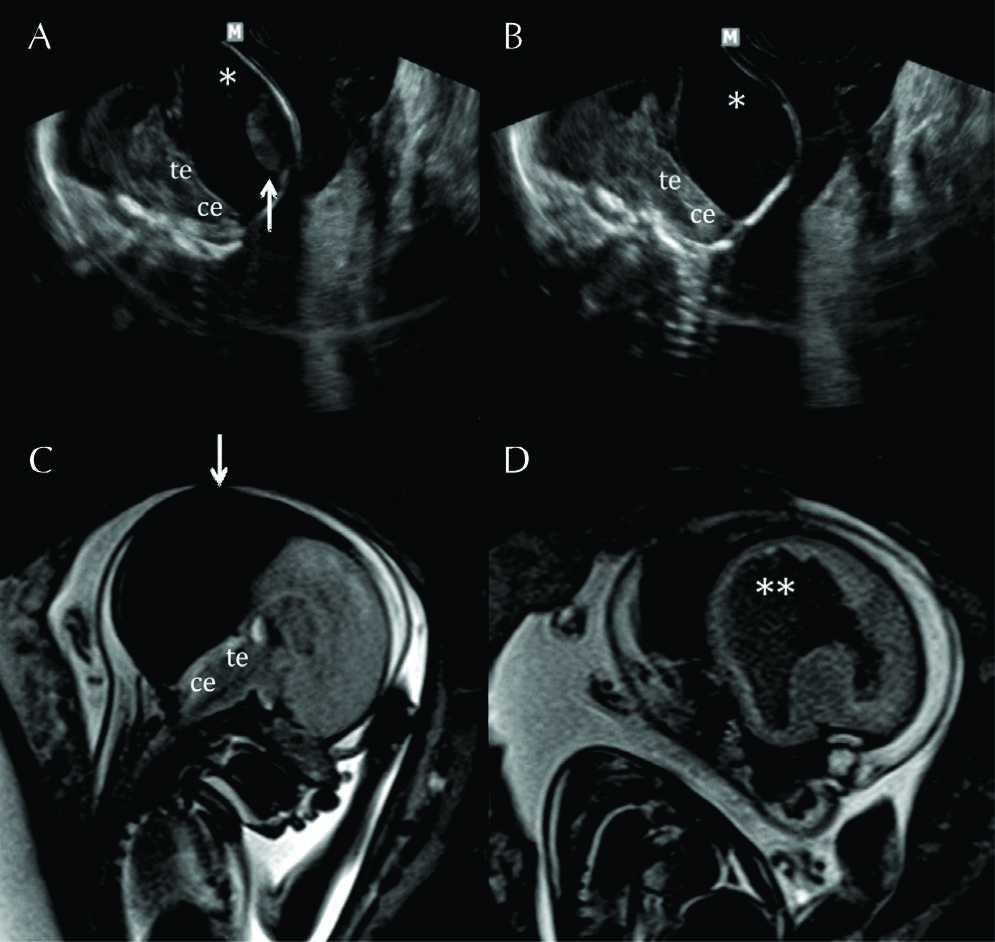

Figura 4

RM Fetal Hidrocefalia por Estenosis del acueducto.

Se presentan 2 casos de fetos con hidrocefalia (HCF) por estenosis del acueducto. El primer caso se presenta con HCF leve/moderada (A sagital y B axial) donde puede observarse la dilatación ventricular supra-tentorial con IV ventrículo normal lo que orienta al diagnóstico de estenosis del acueducto.

En C se muestra imagen sagital del 2º caso con HCF severa y ausencia de señal en el acueducto de Sylvio lo que orienta al diagnóstico (è). AV: Atrio ventricular

CC: cuerpo calloso

Te: Tronco encefálico

Ce: Cerebelo

Figura 5

RM Fetal Hidranencefalia.

RMf a las 29 semanas de edad gestacional en paciente referido para confirmación de hidranencefalia, diagnóstico diferencial de HCF extrema. En A imagen sagital donde se observa la dilatación del sistema ventricular con estructuras de la fosa posterior de anatomía normal al igual que el IV ventrículo.

En B imagen coronal donde se observa la severa dilatación de los ventrículos laterales y se observan ambos tálamos (T) de aspecto normal con 3er ventrículo entre ellos.

En los cortes axiales (C y D) se observan los elementos ya destacados y además se corrobora otra estructura de línea media como la hoz cerebral (HC) y la presencia de escaso manto cerebral a nivel occipital (MC). Esto permite diferenciar esta entidad de las prosencefalias. Te: Tronco encefálico Ce: Cerebelo